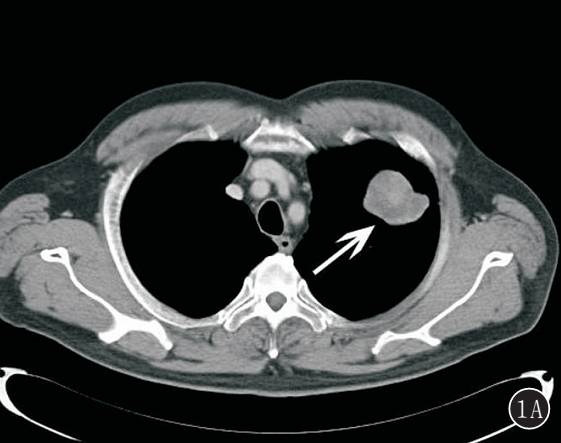

图 2A,B 右下肺纤维肉瘤。 A. 肿块密度不均匀,边缘见分叶征,局部与邻近胸膜关系密切;B. 肿瘤由单一的异型梭形细胞组成,细胞呈较规则的束状排列(HE ×100)